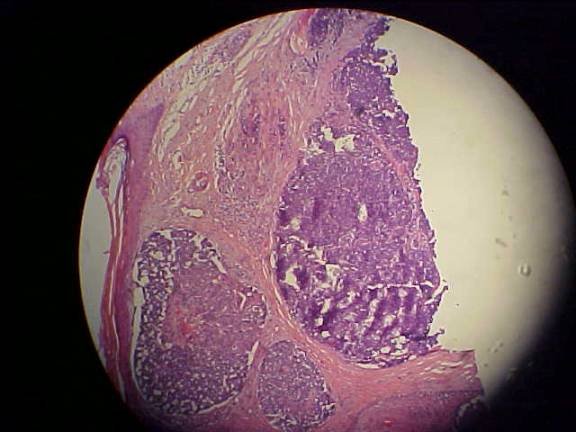

DERMATOHISTOPATHOLOGY:

Poorly differentiated basophilic neoplasm characterized by sheets of atypical basophilic cells, many of which are necrotic and in mitoses. Special stains show that the cells are positive for cytokeratin 20 and neuron-specific enolase. See low low-power and high-power digital photomicrographs below.